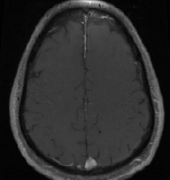

矢状窦旁是 脑膜瘤 生长较常见的部位之一,占全部颅内脑膜瘤的18-23%。矢状窦旁脑膜瘤(PMs)与上矢状窦及引流静脉的紧密联系,使根治性切除难以实现,可能导致神经功能的持续损害,...

Cushing和Eisenhardt将矢状窦旁脑膜瘤定义为肿瘤充填矢状窦旁角,在肿瘤和上矢状窦间无脑组织。对此,国外也有相关的研究数据为证:辛普森I级切除5年后的复发率为35%,II级切除为4%,I...

镰旁和矢状旁脑膜瘤是颅底脑膜瘤的常见部位,切除手术可从根本上解除占位效应,但手术不慎也有可能造成并发症...